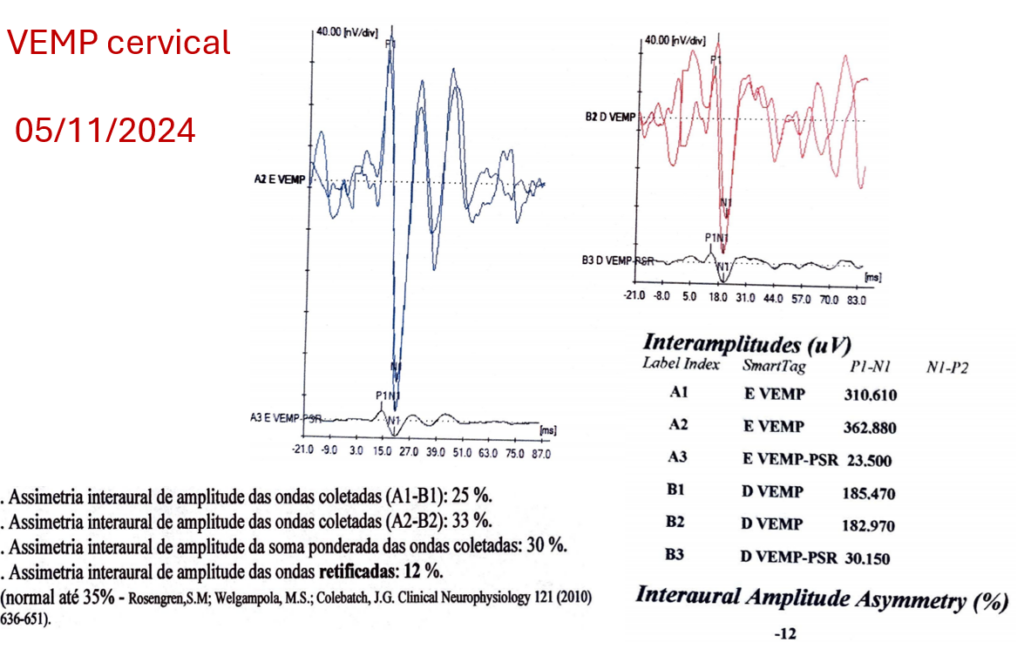

O exame do Vemp cervical mostra claramente que o potencial inibitório P1-N1 permanece presente mesmo com um limiar de estímulo rebaixado na orelha esquerda (Com 55dBnHL tivemos resposta = limiar na orelha esquerda). Isso não ocorreu na orelha direita. Portanto, pelo Vemp cervical, estamos diante de um caso de Síndrome da Terceira Janela Labiríntica acometendo a orelha esquerda (lado mais sintomático).

O exame do Vemp ocular mostra que do lado esquerdo a amplitude N1-P1 está alargada, está maior que 17,1 microvolts e com o estímulo de 4000 Hertz, o potencial excitatório N1-P1 foi registrado (o que não deveria acontecer em orelhas normais). Esses dois achados são descritos na Síndrome da Terceira Janela Labiríntica (Otology & Neurotology, Vol. 42, No. 9, 2021)